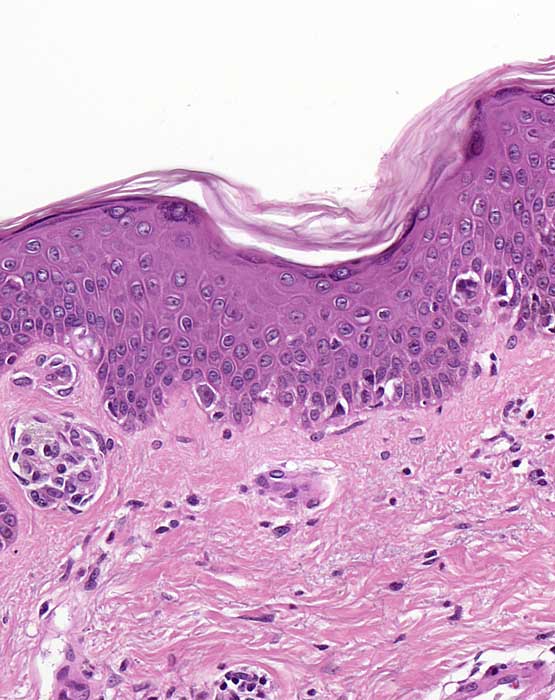

naevoides Melanom: unscharfe laterale Begrenzung

Die laterale Begrenzung des Melanoms ist unscharf. Die laterale Begrenzung wird gebildet durch atypische Einzelzellen und kleine Nester in unregelmässigen Abständen.

Histologie

200